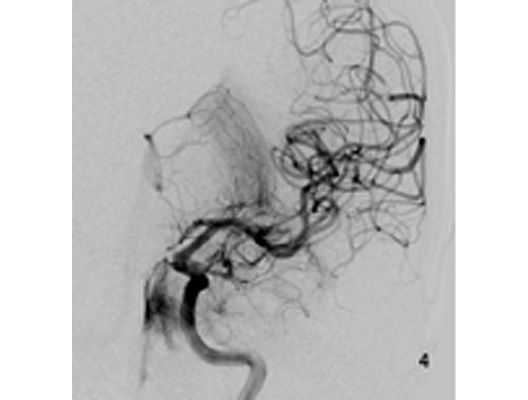

Das Beispiel zeigt die angiographischen Bilder einer Patientin, bei der es zu einer Sehstörung gekommen war. Die Ursache war ein großes Aneurysma der Halsschlagader an der Schädelbasis (Bild 1). Bild 2 zeigt die Lage des Aneurysmas hinter dem Auge. Durch den Druck des Aneurysmas auf den Sehnerv war es zu der Sehstörung gekommen. Die Patientin wurde mit einer speziellen Gefäßprothese versorgt, welche über eine Punktion der Leistenarterie in die Halsschlagader eingesetzt wurde (Bild 3). Bei der Kontrolle nach 6 Monaten zeigte sich ein vollständiger Verschluss des Aneurysmas (Bild 4). Die Sehstörung hatte sich vollständig zurückgebildet.